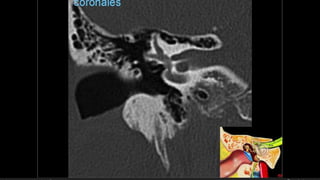

Evaluación Imagenologica

• #38 Izqu. AXIAL-- fxLongitudinal perdonan la capsula otica (laberinto oseo) Centro AXIAL fx trnasversa lascuales tperdonan el lab erinto oseo Dere: MIXTA – tmp perdona